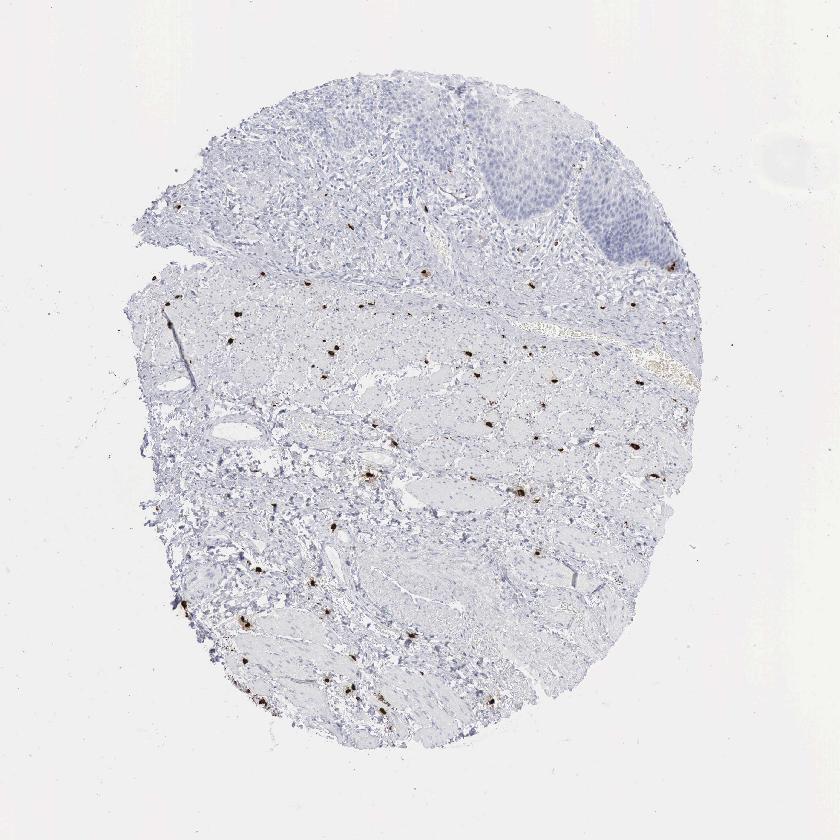

ESOPHAGUS - Antibody stainingi

Antibody staining in the annotated cell types in the current human tissue is reported as not detected, low, medium, or high, based on conventional immunohistochemistry profiling in selected tissues. This score is based on the combination of the staining intensity and fraction of stained cells.

Each image is clickable and will lead to virtual microscopy that enables deeper exploration of all samples and also displays staining intensity scores, fraction scores and subcellular localization as well as patient and tissue information for each sample.

Antibody HPA052634Antibody CAB000363

Squamous epithelial cells Not detectedNot detected